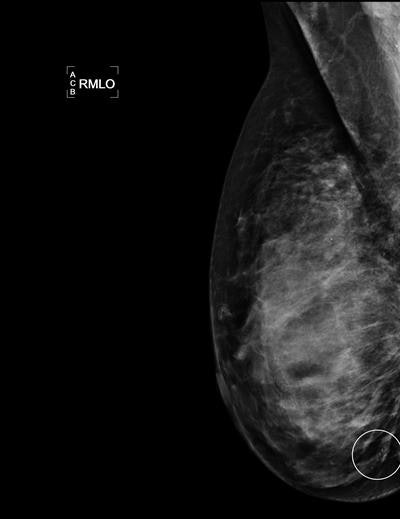

Tabár, who was not involved in the research, cited stellate/spiculated cancers and microcalcifications as being among those detected with a higher sensitivity, while circular/oval-shaped cancers as well as architectural distortion are, although often fast-growing, aggressive cancers, frequently missed.